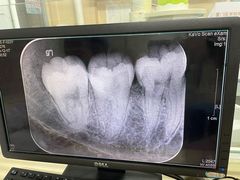

• 厦门医学院附属口腔医院(蔡塘院区)

• -厦门医学院附属口腔医院(蔡塘院区)

匿名用户 | 21-03-03